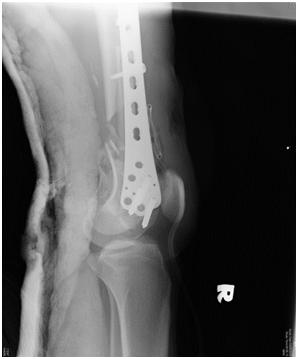

The purpose of this case report is to demonstrate that despite the severity of the injury, good union and functional outcome is achievable using the relatively simple technique of distal femur plating with locking plate augmented with autogenous non-vascularized fibula bone graft.We presented a case of a 20-year-old man who had an alleged motor vehicle accident. He presented to the emergency department with pain and bleeding of the right thigh. On examination, Glasgow Coma Scale score was 15 of 15. There was a deep laceration wound at the anterolateral aspect of his distal right thigh measuring 8cm by 4cm. There was deformity, local tenderness, and abnormal mobility in the distal part of the thigh but no distal neurovascular deficit. Radiographs of the right femur revealed a severely comminuted supracondylar fracture with bone loss and intraarticular involvement (Figure 1A & 1B). The fracture was classified as AO type 33-C3.

Postoperative radiograph showed acceptable fracture alignment with autogenous fibular graft inside the medullary canal (Figures 2A & 2B).